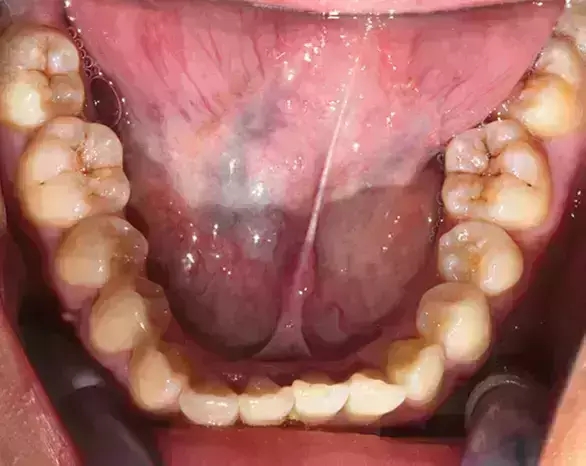

Damon 病例分享:安氏 II 類(lèi)二分類(lèi)露齦笑的矯治(董一磊)

患者信息

治療前后對(duì)比